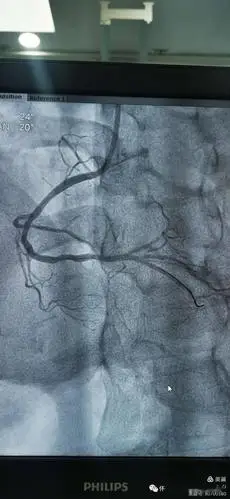

冠脉造影提示:左冠状动脉的前降支也有重度狭窄